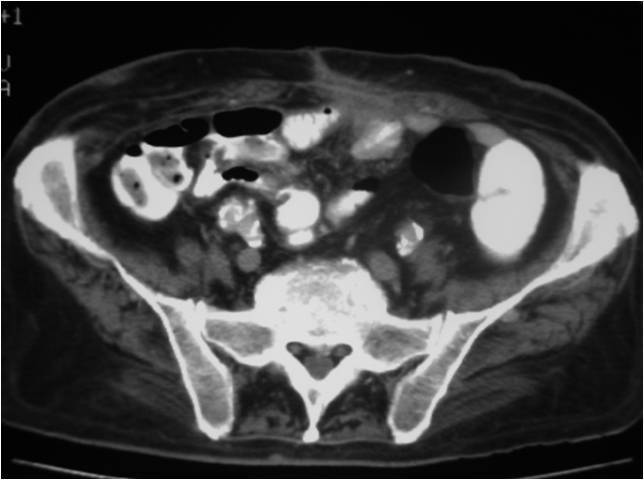

- Placement of a nephrostomy and sump caheter through the greater sciatic foramen into a deep pelvic abscess.

- Paracentisis of a deep pelvic abscess

- Successful catheter placement in a deep pelvic abscess